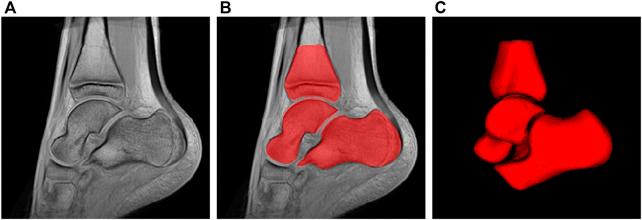

Cerebral palsy, a common physical disability in childhood, often causes abnormal patterns of movement and posture. To better understand the pathology and improve rehabilitation of patients, a comprehensive bone shape analysis approach is proposed in this article. First, a group analysis is performed on a clinical MRI dataset using two state-of-the-art shape analysis methods: ShapeWorks and a voxel-based method relying on Advanced Normalization Tools (ANTs) registration. Second, an analysis of three bones of the ankle is done to provide a complete view of the ankle joint. Third, a bone shape analysis is carried out at subject level to highlight variability patterns for personnalized understanding of deformities.

脑瘫是儿童期常见的身体残疾,常导致异常的运动和姿势模式。为了更好地理解其病理并改善患者的康复情况,本文提出了一种全面的骨骼形状分析方法。首先,使用两种先进的形状分析方法对临床MRI数据集进行组分析:ShapeWorks和基于体素的方法(该方法依赖于高级归一化工具(ANTs)配准)。其次,对踝关节的三块骨头进行分析,以全面了解踝关节。第三,在个体层面进行骨骼形状分析,以突出变异模式,从而个性化地理解畸形情况。